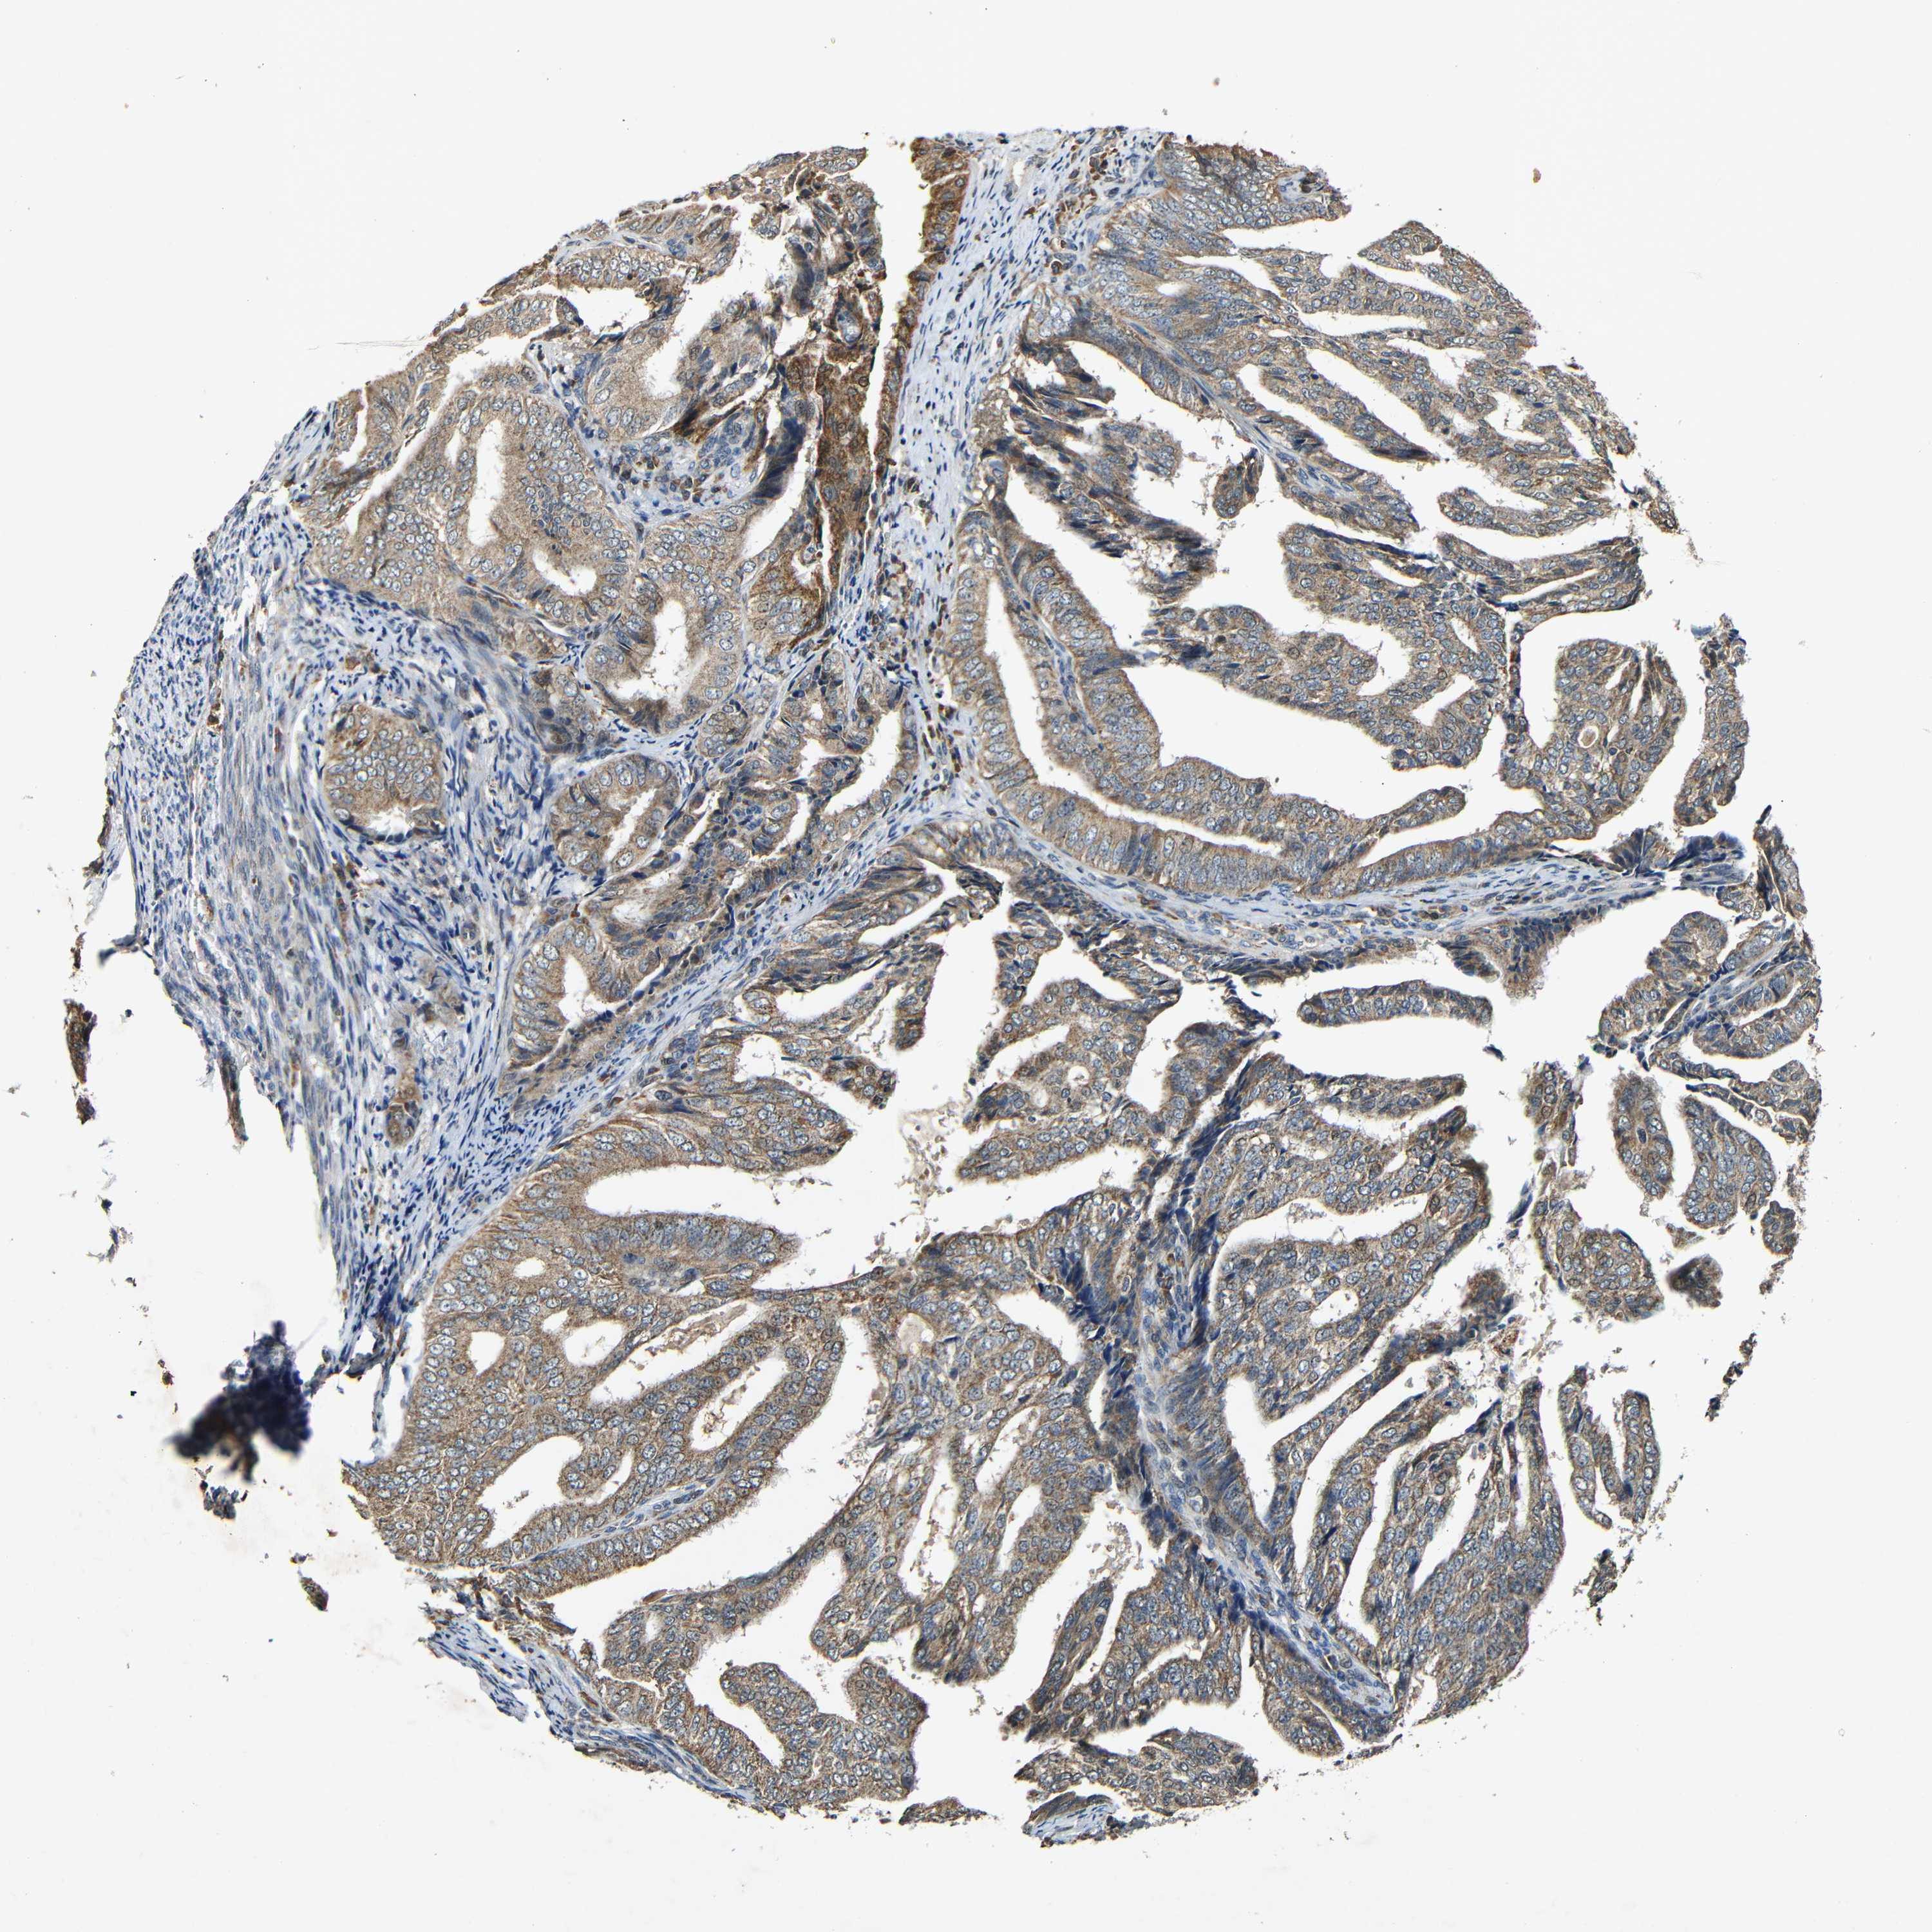

ENDOMETRIAL CANCER - Protein expressioni

A mouse-over function shows sample information and annotation data. Click on an image to view it in a full screen mode. Samples can be filtered based on level of antibody staining by selecting one or several of the following categories: high, medium, low and not detected. The assay and annotation is described here.

Note that samples used for immunohistochemistry by the Human Protein Atlas do not correspond to samples in the TCGA dataset.

Antibody stainingi

Antibody staining in the annotated cell types in the current human tissue is reported as not detected, low, medium, or high, based on conventional immunohistochemistry profiling in selected tissues. This score is based on the combination of the staining intensity and fraction of stained cells.

Each image is clickable and will lead to virtual microscopy that enables deeper exploration of all samples and also displays staining intensity scores, fraction scores and subcellular localization as well as patient and tissue information for each sample.

Antibody HPA011800

Staining

High

Medium

Low

Not detected

Intensity

Strong

Moderate

Weak

Negative

Quantity

>75%

75%-25%

<25%

None

Location

Nuclear

Cytoplasmic/membranous

Cytoplasmic/membranous,nuclear

Adenocarcinoma, NOS